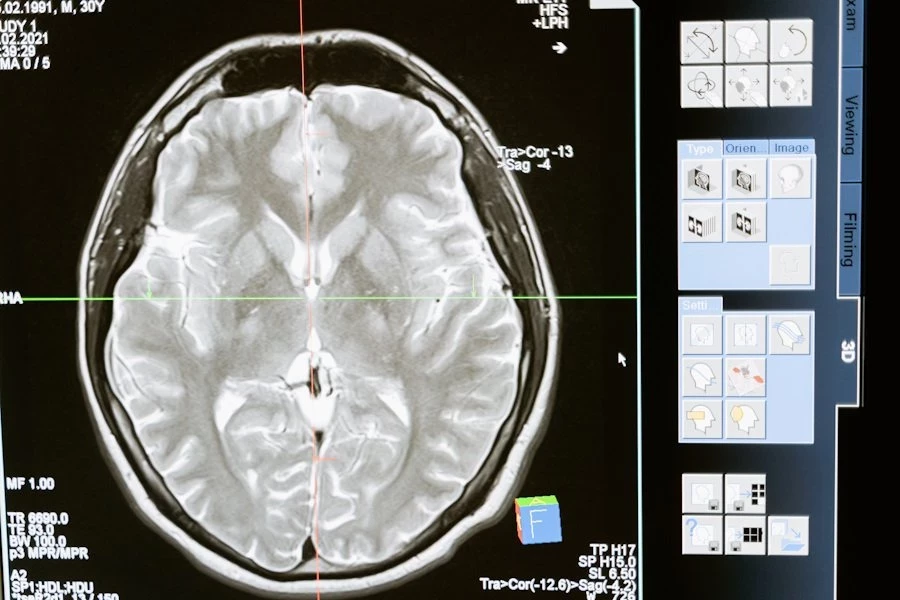

Ученые из Universitat Pompeu Fabra (Испания) сделали удивительное открытие: объем зрительной рабочей памяти человека можно увеличить с помощью звуковой и визуальной стимуляции. Это открытие открывает новые перспективы в улучшении когнитивных способностей и, возможно, лечении ряда заболеваний, сообщает Communications Psychology.

Зрительная рабочая память — это система мозга, которая помогает нам временно удерживать важные визуальные детали, например, при чтении, решении головоломок или сравнении объектов. Исследователи опирались на тета-гамма-модель, которая связывает объем рабочей памяти с частотой тета-колебаний мозга. Эти ритмичные волны появляются в переходе от бодрствования к расслаблению.